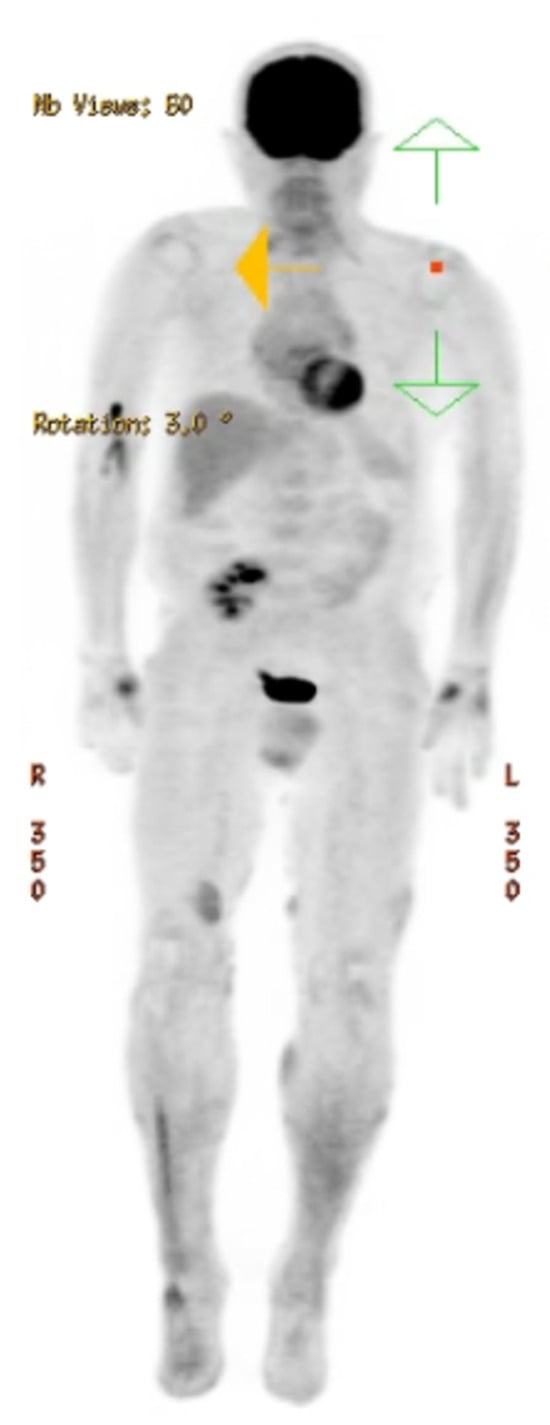

2. Case Report

| Our patient | M/45 y | Paresthesia, tingling, numbness and edema of the little and ring fingers | Two years/ two years | Surrounding soft tissue | R-CHOP chemotherapy + radiotherapy | Remission |